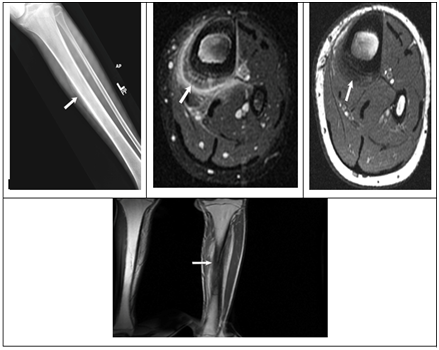

Figure 1 Patient 1 Imaging review.

1. Figure 1A: AP view X-ray of the tibia demonstrating increased sclerosis of the proximal tibia.

2. Figure 1B: Coronal T1 MRI showing bone marrow edema and cortical sclerosis.

3. Figure 1C: Coronal T2 MRI showing bone marrow edema and cortical sclerosis.

4. Figure 1D: Coronal non-contrast CT scan demonstrating increased sclerosis in the proximal tibia.

5. Figure 1E: Tc99m Bone scan showing increased uptake in the right proximal tibia.